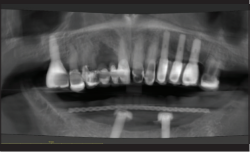

The patient presented with a history of dental implants in the maxillary and mandibular arches. The remaining maxillary dentition exhibited failure, chronic infection, and inflammation.

Preoperative radiograph Patient pre-op, retracted